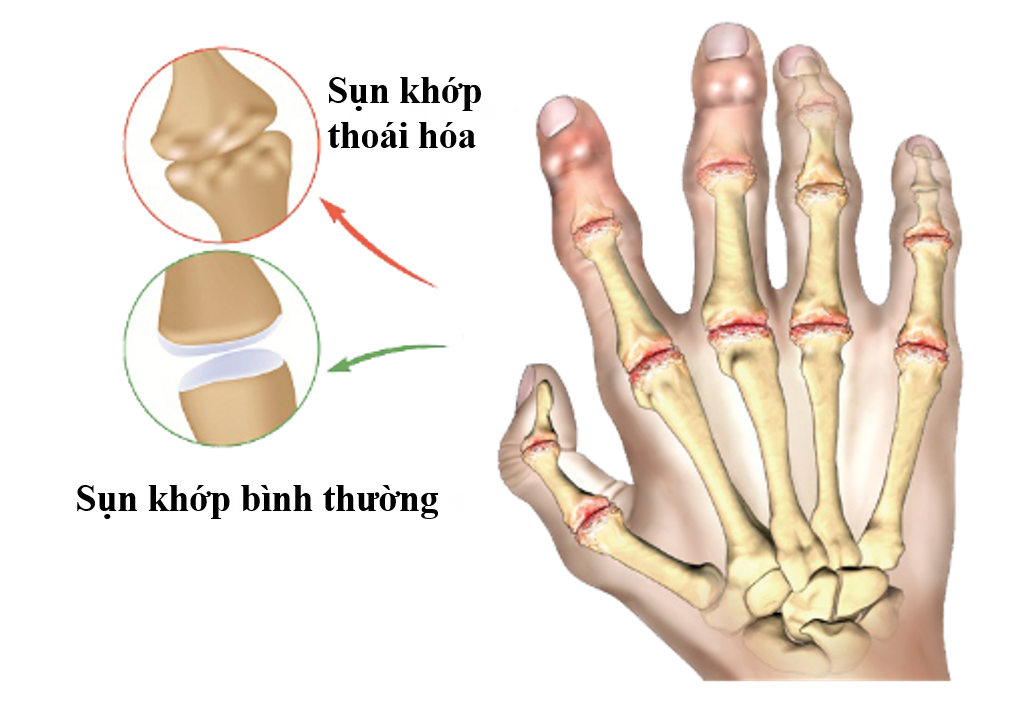

Thoái hóa khớp ngón tay thường gặp ở nhóm từ 60-65 tuổi. Bệnh dễ xảy ra ở bên tay thuận và gặp nhiều ở các ngón trỏ, ngón cái và ngón giữa.

Như bệnh thoái hóa khớp nói chung, nguyên nhân gây bệnh chủ yếu là do sự thoái hóa của cơ thể kèm theo sự lão hóa và bào mòn của sụn khớp[2] ngón tay. Làm cho khoảng không gian giữa 2 xương hẹp lại, ma sát với nhau, dịch khớp mất nguồn cung cấp và ít dần, gai xương hình thành. Hậu quả gây đau, cứng và khó vận động ở ngón tay, cổ tay. Để nhận biết cần dựa vào các triệu chứng sau: